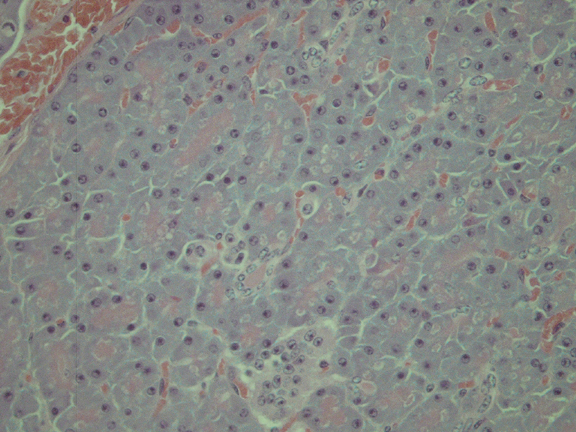

Pancreas from Case 2              Normal pancreas (deer)

Haematoxylin & Eosin (x400)